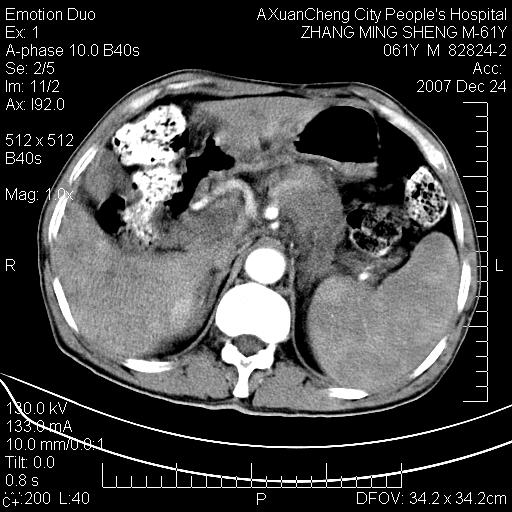

标题: CT11031:M61Y,胰腺占位

大家侃侃门静脉和胆管系统怎么回事,肝内转移?

1,肝硬化,脾大.

2,肝内多发结节状低密度占位,伴门脉及肠系膜上v栓子形成.考虑a;门脉及肠系膜上v血栓后肝改变.b;弥漫型肝癌伴门脉及肠系膜癌栓.

肝硬化,门脉高压,脾肿大;弥漫性肝癌,肝内、门脉、腹膜后淋巴结转移,肝内外胆管扩张,胰头区占位,建议mr检查

胰腺癌伴肝内转移;门脉、肠系膜上v癌栓形成。

考虑为:胰腺癌伴肝脏转移、腹膜后淋巴结转移,门静脉及肠系膜上静脉瘤栓形成。

胰体尾癌伴肝内转移,门静脉及肠系膜上静脉瘤栓形成.

肝硬化,脾大. 胰腺癌伴肝内转移;门脉、肠系膜上v癌栓形成。